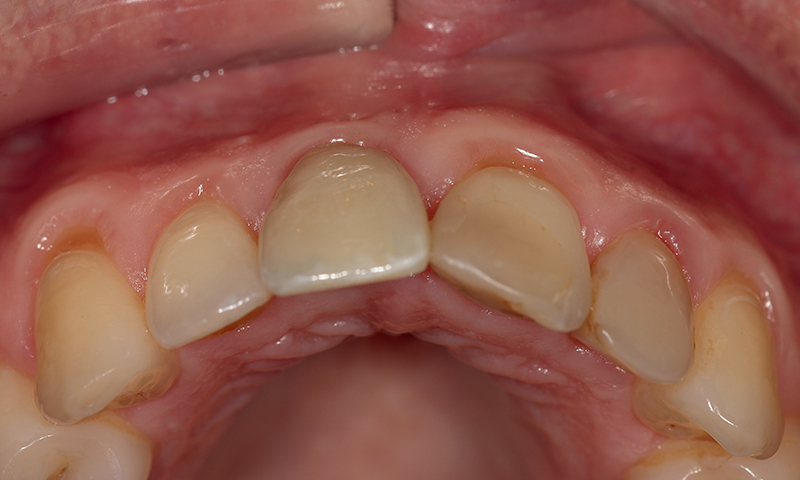

Fig. 11 (caso 3) - Quadro clinico iniziale

Caso 3: Un paziente maschio subiva un trauma durante l'infanzia e si presentava con una fistola associata al dente 11 e un difetto della cresta alveolare vestibolare. Il paziente era sottoposto a posizionamento immediato di un impianto SDS. In questo caso, l'aumento veniva combinato con il prelievo di tessuto connettivo subepiteliale (SCTG) dal palato, attraverso una singola incisione, tunnellizzazione buccale e inserimento dell’innesto. I successivi appuntamenti di follow-up rivelavano il successo della preservazione della cresta alveolare vestibolare, e della guarigione dei tessuti molli attorno all'impianto. L'osteointegrazione avveniva senza problemi e si poteva iniziare la pianificazione della corona definitiva. Questo caso era seguito per 5 anni e anche dopo questo periodo il contorno alveolare era estremamente soddisfacente. La guarigione e la gestione dei tessuti molli erano adeguate, suggerendo come l'applicazione dell'innesto di tessuto connettivo abbia contribuito positivamente al risultato estetico (Fig. 11-17).